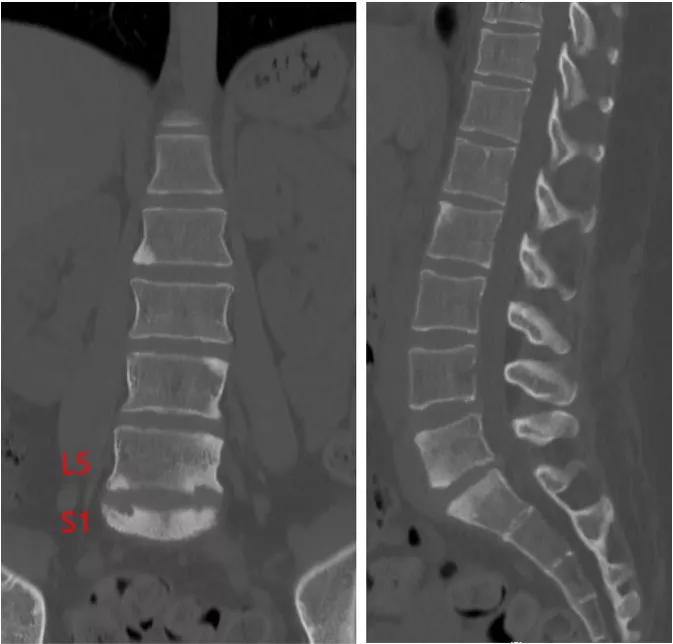

数年前より腰痛が出現した。臥床時の腰痛が最も辛く、起き上がりが困難であった。仕事中など日中に体を動かしている間は腰痛は気にならなかった。腰痛は年々悪化したため近医整形外科を受診した。CRP 1.31mg/dlと炎症反応上昇があり、腰椎CTでL5/S1を主とした椎体の硬化像やびらんを認めた(写真1)。

写真1 腰椎CT 正面像 側面像